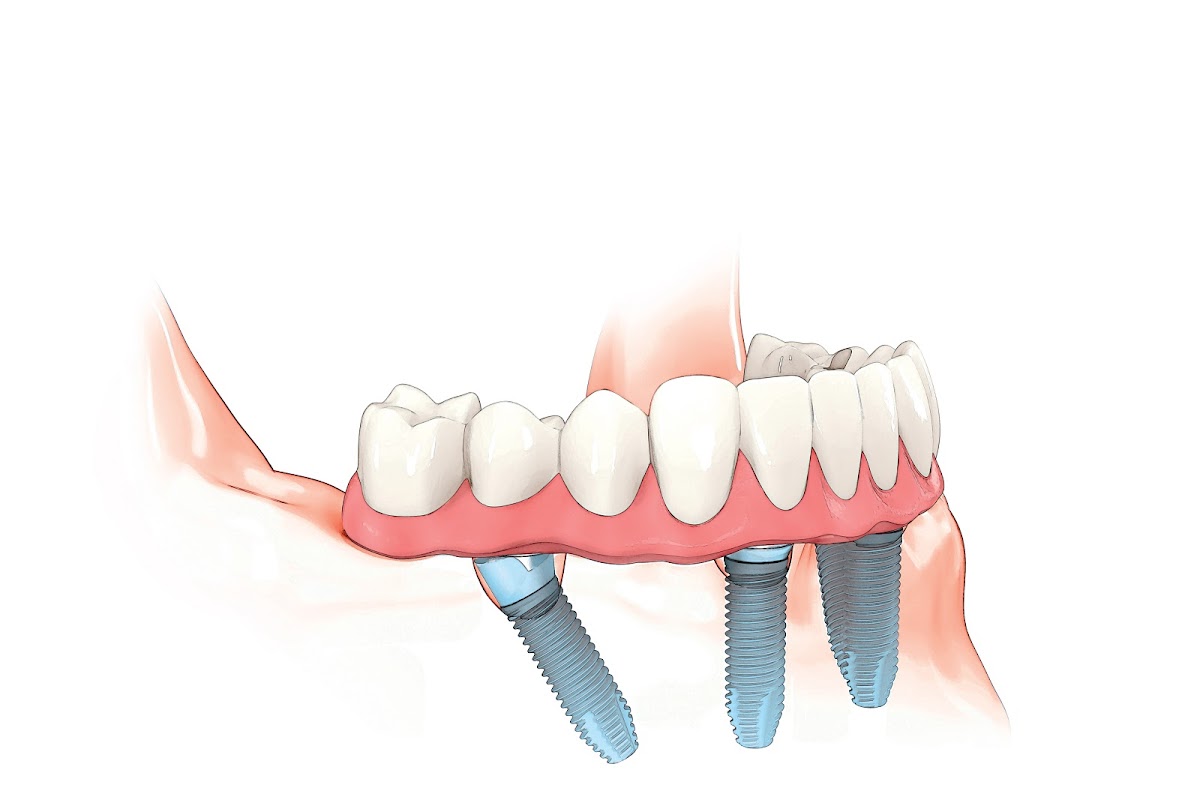

Nestled within the prestigious Upper East Side neighborhood of Manhattan, at 250 East 63rd Street, a distinguished dental practice once served the New York community with a legacy of excellence, though it is now closed. This practice, which operated for several decades, established itself as a cornerstone of high-end, comprehensive dental care in one of the city's most discerning zip codes. Its history is intertwined with the evolution of modern dentistry, transitioning from a traditional family practice to a state-of-the-art clinic that embraced the latest technological advancements while maintaining an unwavering commitment to personalized, compassionate care. The mission was always clear: to provide exceptional, ethical, and aesthetically focused dental services in a comfortable and anxiety-free environment, ensuring each patient felt like a valued individual rather than just a case file. The practice catered to a sophisticated clientele, including long-time neighborhood residents, professionals, and families, who sought not only clinical excellence but also discretion, reliability, and a holistic approach to oral health. The expertise of the founding and subsequent dentists spanned the full spectrum of general, restorative, and cosmetic dentistry, with a particular reputation for meticulous cosmetic smile makeovers, advanced implantology, and complex full-mouth rehabilitation. What set this practice apart was its unique value proposition of combining the artisanal skill of a boutique practice with the technological capabilities of a large institution. It was known for its serene, elegantly appointed office—a stark contrast to the sterile, clinical feel of many dental offices—featuring curated art, comfortable amenities, and a staff dedicated to creating a warm, welcoming atmosphere. The dentists were not merely technicians but educators and partners in their patients' long-term health, investing time in detailed consultations and clear communication. This patient-centric philosophy, rooted in trust and long-term relationships, was the bedrock of its reputation. In a city teeming with dental options, this practice distinguished itself through its consistency, its integration of cutting-edge digital dentistry (such as intraoral scanners, CAD/CAM same-day crowns, and 3D imaging) into a personalized care model, and its collaborative approach, often working with a network of top-tier dental specialists in periodontics and orthodontics to ensure seamless, coordinated treatment. The legacy of this now-closed location is one of a trusted community institution that elevated the standard of dental care, leaving a lasting impression on its patients through its dedication to excellence, artistry in dentistry, and profound respect for the person in the chair. Its closure marks the end of an era for those who relied on its exemplary service.